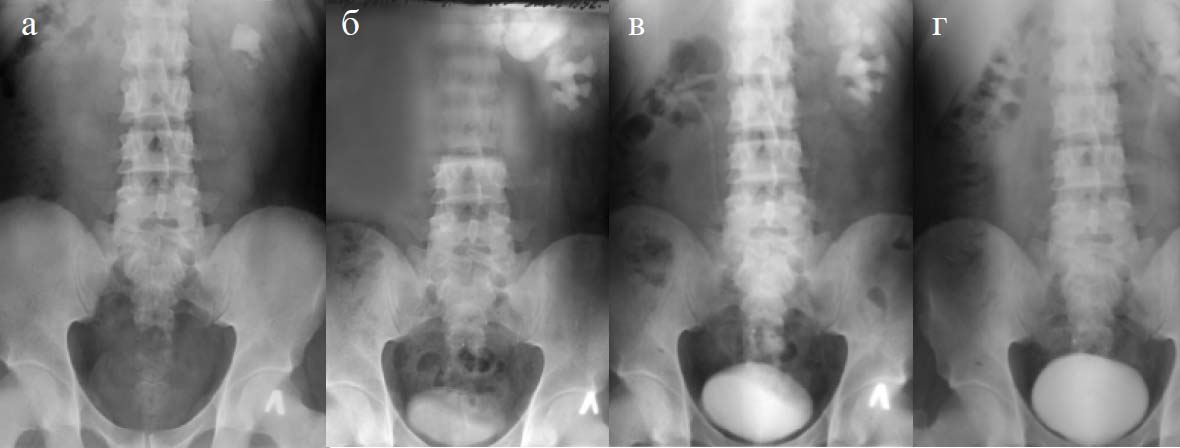

Экскреторная урография. На обзорной урограмме в проекции левой почки на уровне позвонков ThXII–LIII видны тени (КН) размером 2,5×2,5 см, охватывающие всю лоханку и шейку чашек, а также множественных мелких камней разных размеров в нижней группе чашек. В проекции правой почки нет теней, подозрительных на камень (рис. 2, а).

Рис. 2. Пациент Г.С. Данные экскреторной урографии (ЭУ): а — обзорная урограмма; б — ЭУ на 15-й минуте; в — ЭУ на 30-й минуте; г — ЭУ на 60-й минуте

На экскреторной урограмме, снятой на 15-й минуте, видно накопление контрастного вещества в обеих почках. На обеих сторонах внутрипочечная лоханка, ЧЛС справа в норме, а слева — резко расширена. Левый мочеточник не визуализируется (рис. 2, б).

На экскреторной урограмме, снятой на 30-й минуте, функционирование правой почки удовлетворительное. Мочеточник визуализируется местами. ЧЛС слева резко расширена, левый мочеточник не визуализируется (рис. 2, в).

На урограмме, снятой через час, левая почка полностью опорожнена. ЧЛС слева не опорожняется. Визуализируется верхняя треть мочеточника (рис. 2, г).